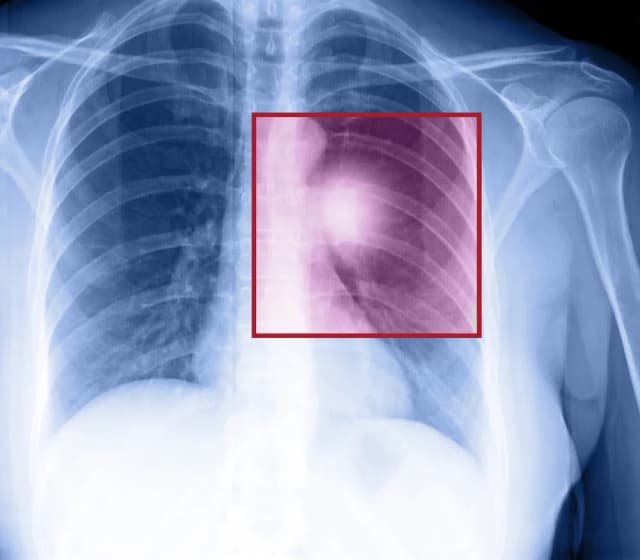

Rak mostka: 7 alarmujących objawów, które musisz znać

Poznaj 7 kluczowych objawów raka mostka, które mogą uratować Ci życie. Dowiedz się, jak rozpoznać niepokojące symptomy i kiedy zgłosić się do lekarza. Nie ignoruj tych sygnałów!